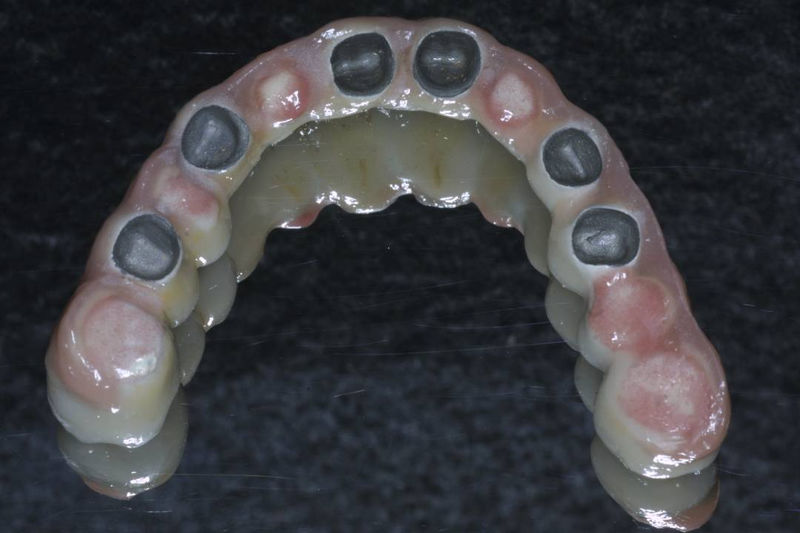

Restauraciones fabricadas en el laboratorio los cuales se usan para reemplazar dientes ausentes en toda una arcada usando implantes y/o tejidos blandos como soporte y que pueden y deben de ser removidas para su limpieza. Para poder enviar el caso al laboratorio se toman impresiones utilizando materiales de impresión o técnicas modernas digitales.

Son estructuras de titanio las cuales se colocan en el hueso y se utilizan para soportar coronas, prótesis fijas, removibles y totales. La colocación de los implantes se hacen previo análisis tomográfico.